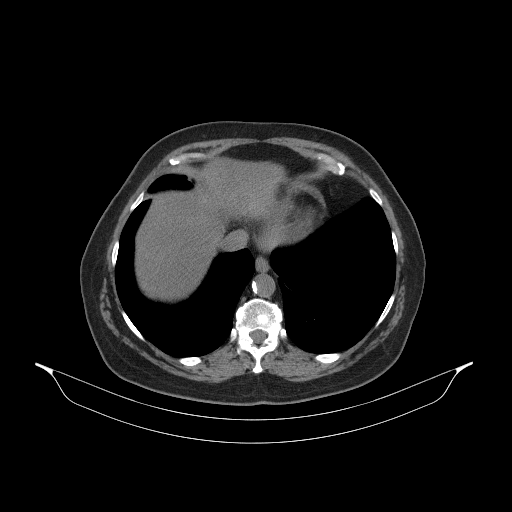

Original NATIVE CT scan (input)

Full window (WL 1023.5, WW 4095 β†’ Low βˆ’1024, High +3071)

Actual HU range: [-160.0, 240.0]

Lung window (WL -600, WW 1500 β†’ Low βˆ’1350, High +150)

Actual HU range: [-160.0, 150.0]

Mediastinum window (WL 40, WW 400 β†’ Low βˆ’160, High +240)